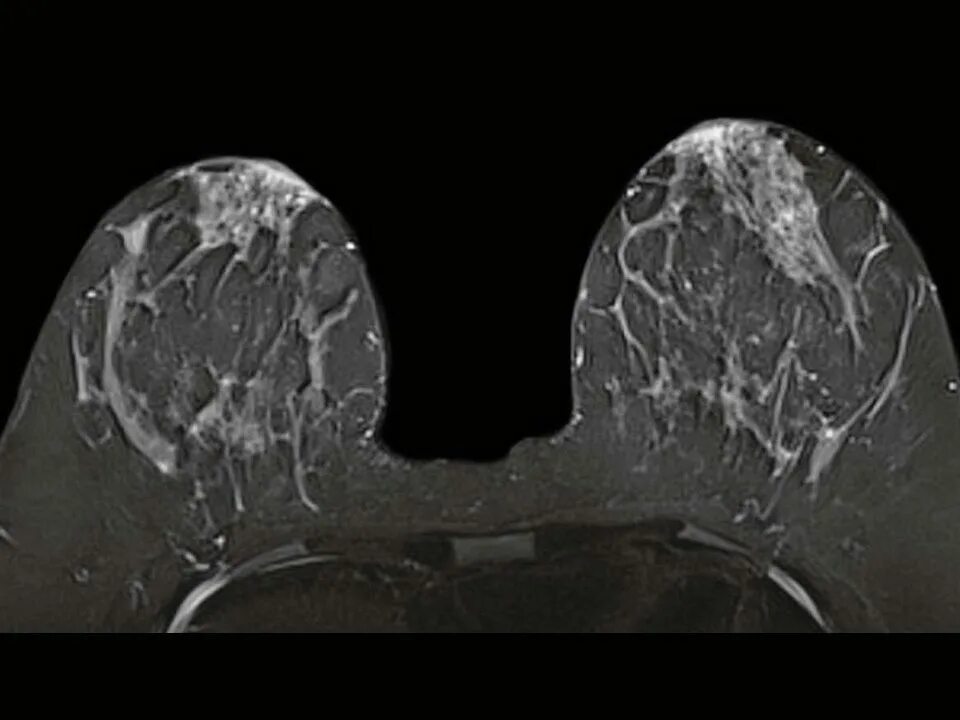

Мрт молочных желез